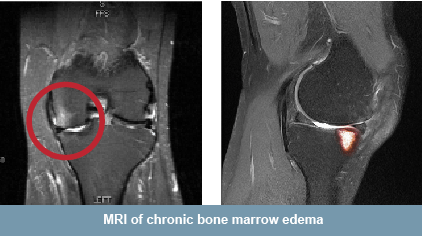

Chronic BME is a defect of the bone typically 0-10 mm below the cartilage. Chronic BME is characterized by an area of inflamed edema surrounding micro fractures or defects. Many surgeons believe that chronic BME will not heal without treatment.

Chronic BME can only be seen on MRI.